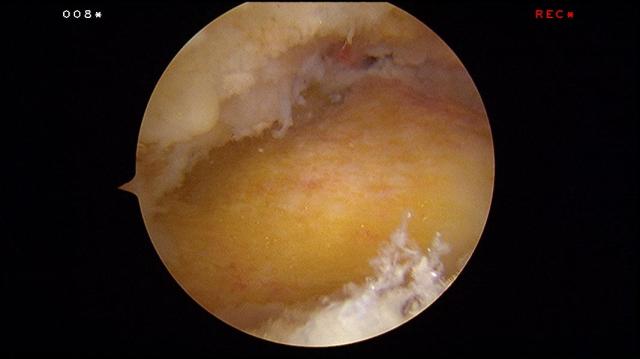

Upon completion of the procedure, the exostosis should be flattened and the insertion of the Achilles tendon into the heel bone should be clearly seen.

An intra-operative fluroscopy (x-rays) is taken to confirm complete removal of the Haglund’s protruberance.